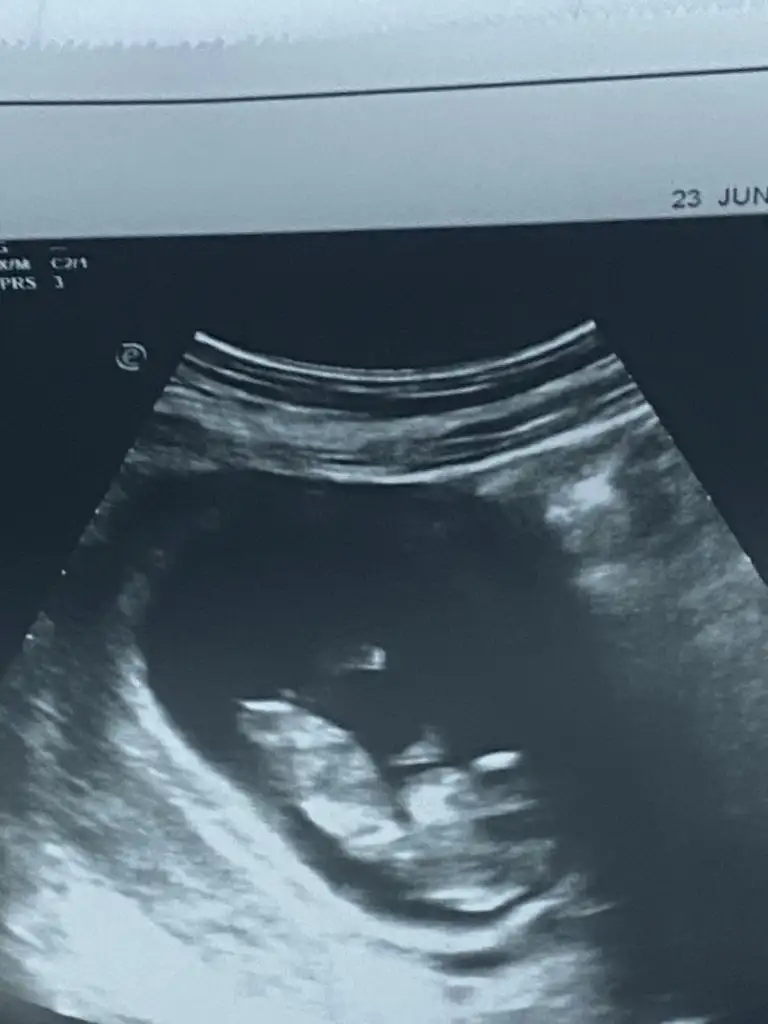

Merhaba teyzoşlarr 12. Haftadaydık ama 4 gün önden gidiyormuşuz 13. Haftadayız. Ve tabiki cinsiyet tahmini yapmadı ikili testi de verdim bakalım hayırlısı, inş hepimizinki sağlıkla gelir.

Merhaba teyzoşlarr 12. Haftadaydık ama 4 gün önden gidiyormuşuz 13. Haftadayız. Ve tabiki cinsiyet tahmini yapmadı ikili testi de verdim bakalım hayırlısı, inş hepimizinki sağlıkla gelir. Eki Görüntüle 3265200